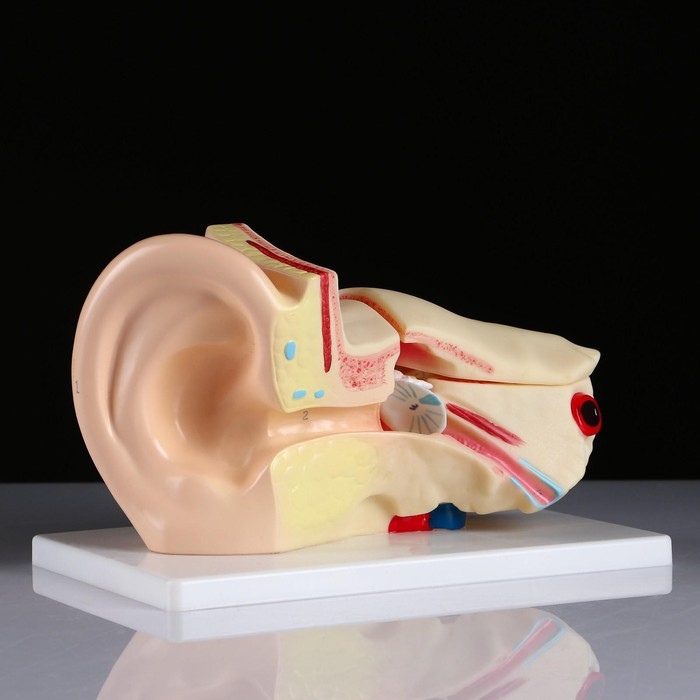

Анатомические модели

ЕКБ 41

No Brand, артикул: 7072360